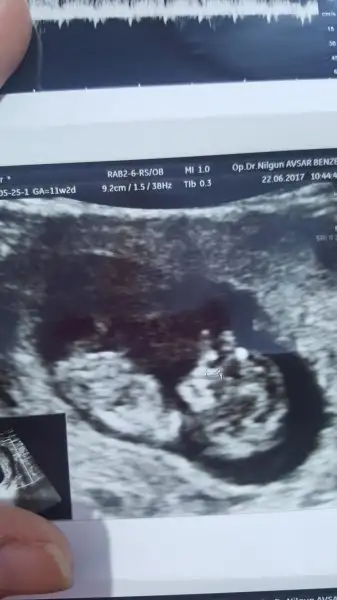

4 yil oncesinden kendimi buldum. Oglumda tutturamadik ama azimliyim 12. Hafta ultrasonuyla bu sefer yeniden dener miyizEki Görüntüle 2012571 kizlar var mi bi fikriniz